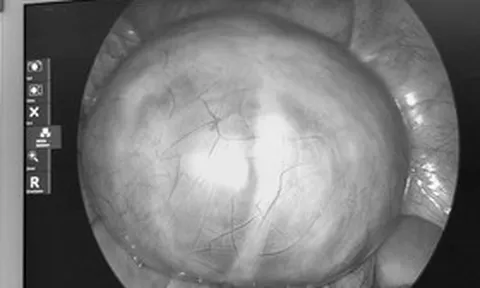

Nam thanh niên 26 tuổi phát hiện suy thận bởi dấu hiệu "vừa lạ vừa quen" ở mắt